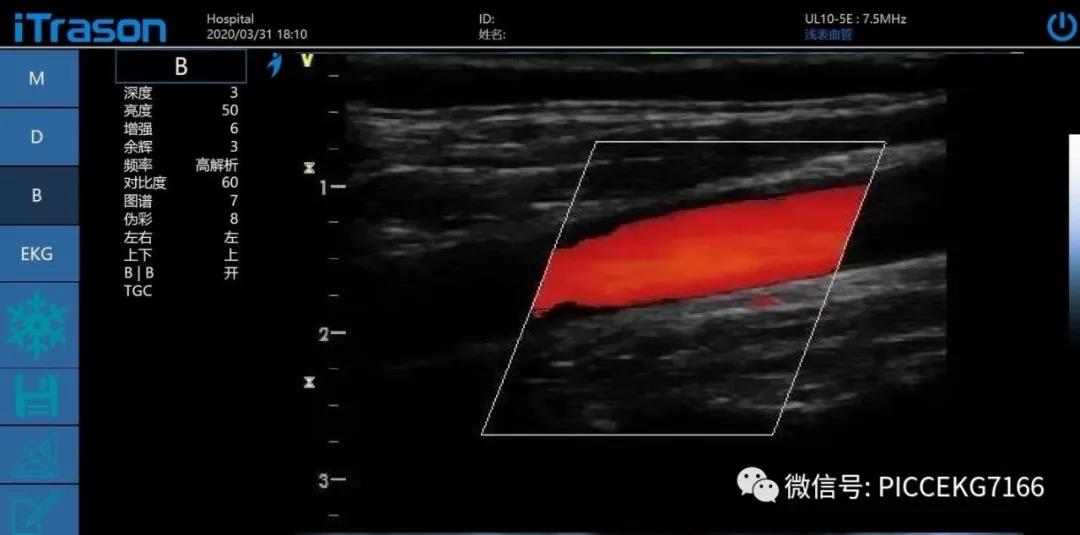

利用“动脉血为离心血,静脉血为回心血”为依据。具体操作如下(颈静脉和颈动脉为例): 血流方向:朝向探头流动的血流呈红色,背离探头流动的血流呈蓝色。并不是红色就一定是动脉,蓝色就一定是静脉,这个是重点:

将探头扫查血管方向倾斜指向患者头侧,由以上内容得到,此时动脉的血流颜色应为红色,静脉血流应为蓝色显示。